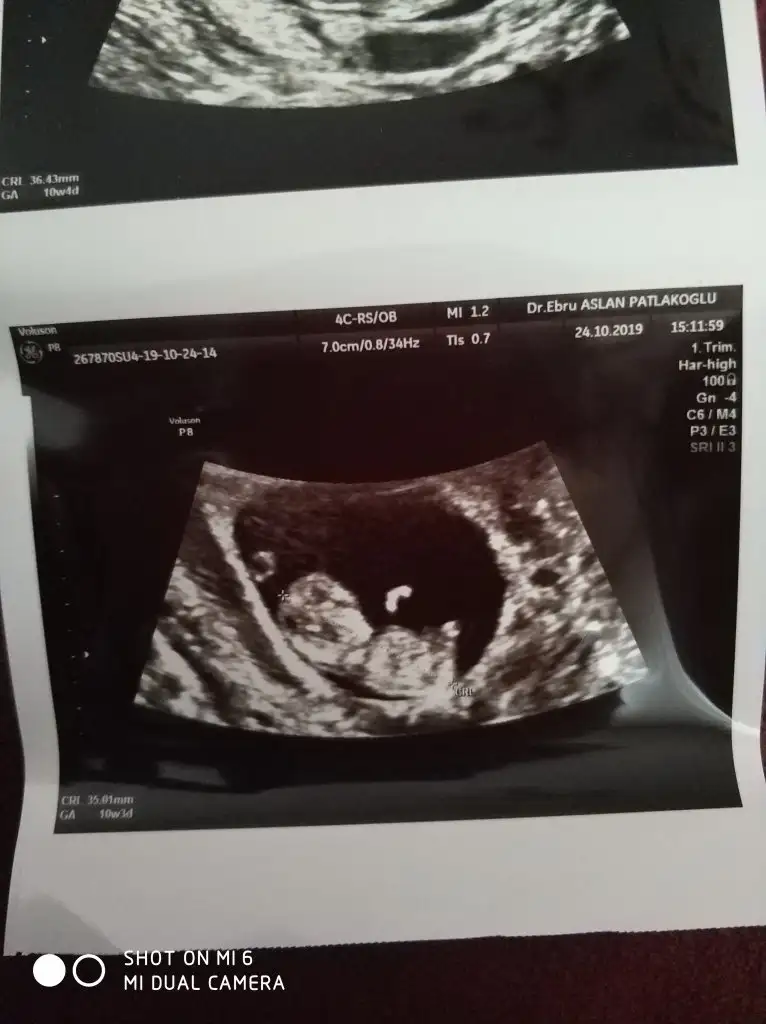

Arkadaslar bunlarda benim cift yumurta ikizlerimin 10. Hafta ultrason goruntuleri. Lutfen bana da yorum yapin![]()

İkiside erkek gibi nub 10 haftada 2 tarafa benzer siz 11 yada 12 hafta usg paylaşınEki Görüntüle 2550233Eki Görüntüle 2550242![]()